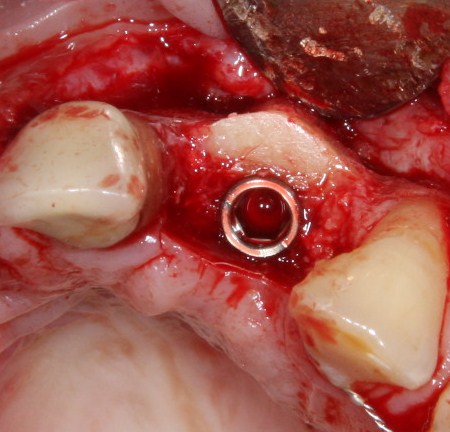

Для решения поставленной клинической задачи мы выбрали имплантационную систему Xive. Из имеющихся у нас трёх имплантационных систем, она лучше всего подходит для немедленной имплантации и немедленной нагрузки, и вот, почему:

В процессе ирригации лунки промываются, что позволило нам еще раз подтвердить ранее сделанные выводы. С помощью аналогов имплантатов, входящих в хирургический набор Xive, мы проверили возможность стабилизации имплантатов в будущих лунках. Исходя из правил подбора и позиционирования имплантатов (я очень рекомендую почитать об этом здесь>>) мы остановились на Xive S диаметром 3,4 мм и длиной 13 мм.

По ряду уже упомянутых выше причин, для решения этой клинической задачи мы выбрали имплантаты Xive. Лунки для них мы уже приготовили. возможную первичную стабильность оценили. Имплантаты мы установили с усилием чуть больше 15-20 Нсм — такого крутящего момента более, чем достаточно, особенно если учесть, что временные коронки будут соединяться между собой.

После перкуторной проверки стабильности имплантатов и точности позиционирования, мы переходим к следующему этапу — сохранению десневого контура.